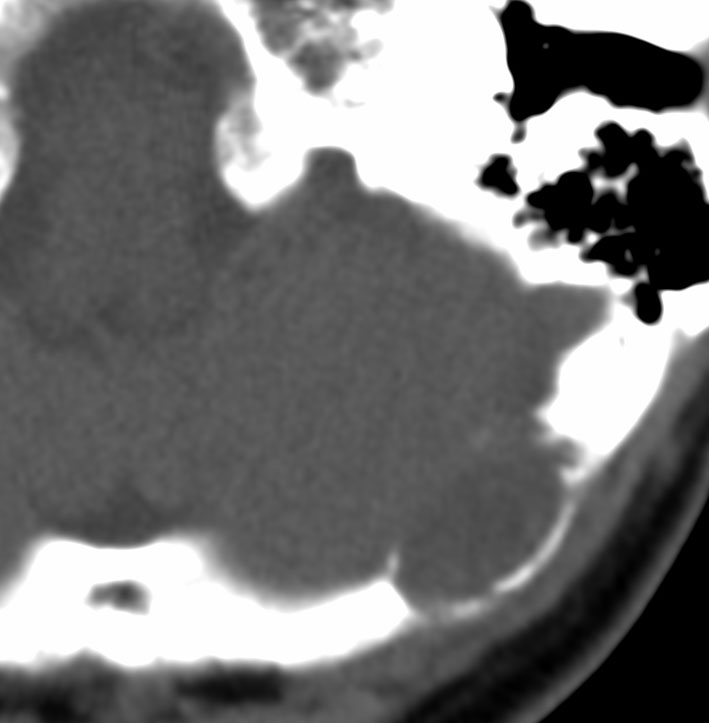

60代女性に偶然発見されたもので,小さな髄膜腫のようにみえ経過観察されました。5年間の経過で徐々に増大しました。

硬膜から発生してと頭蓋骨内に浸潤して骨破壊を伴いながら増殖する腫瘍でした。周囲の硬膜と頭蓋骨削除をして全摘出できました。グレード2のSFTです。このようなものは感全摘出で完治します。